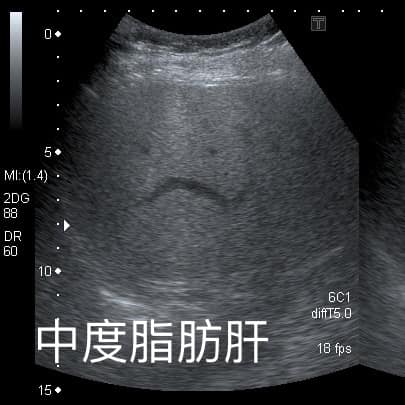

錢政弘醫師在臉書粉絲專頁分享脂肪肝相關案例。60多歲的女病患本來有中度脂肪肝,來照超音波檢查,「肝臟完全正常,脂肪消失了」。一問之下發現阿姨從1年前的66公斤慢慢瘦到51公斤,最近才稍微復胖到56公斤。錢醫師追問阿姨減重成功的祕訣,阿姨表示:「我就少吃水果!」錢醫師一聽倍感驚訝:「少吃水果就可以瘦這麼多!」

肝臟有脂肪在超音波下顏色偏白,翻攝自臉書 (錢政弘 胃腸肝膽科醫師) ,下同。

▲錢醫師說明:脂肪消失後肝臟就恢復深色。